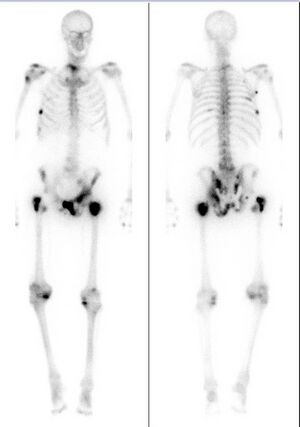

Extent of cancer spread is assessed by MRI or PSMA scan – a positron emission tomography (PET) imaging technique where a radioactive label that binds the prostate protein prostate-specific membrane antigen is used to detect metastases distant from the prostate.[12][8] CT scans may also be used, but are less able to detect spread outside the prostate than MRI. Bone scintigraphy is used to test for spread of cancer to bones.[12]